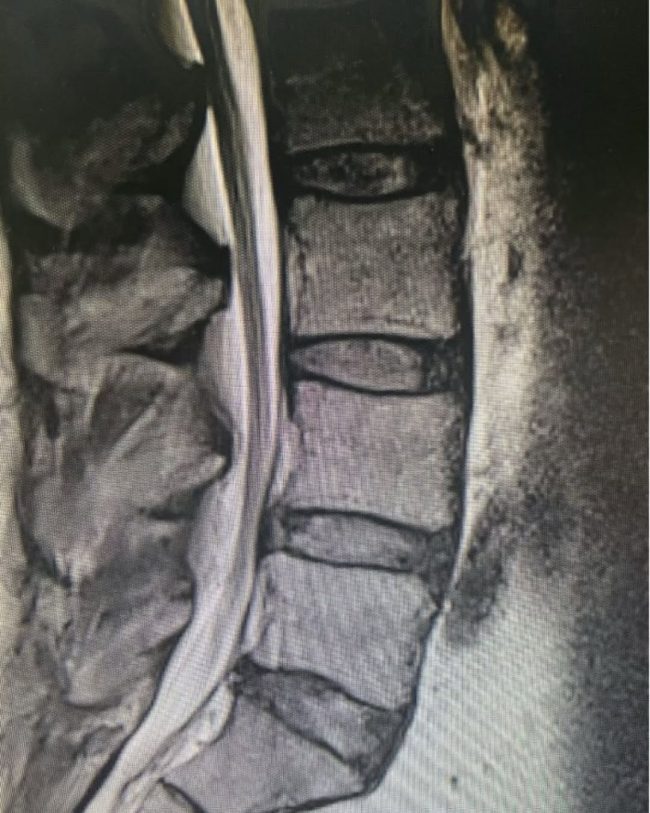

89-Year-Old with C5–6 Fracture-Dislocation: Surgical Stabilization

“Taking a call at a Level 1 trauma center is stressful and takes time away from family and a neurosurgeon’s precious free time. I was reminded recently why I still feel passionate about taking a Level 1 trauma call when I met this simply miraculous 89-year-old woman. She was involved in a motor vehicle collision…